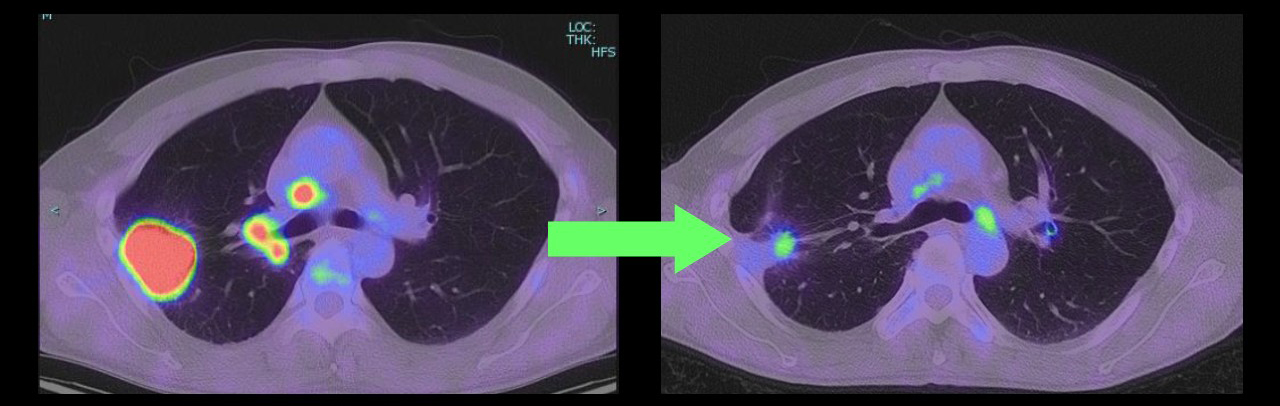

【症例1】下図左)右上葉の病変は胸壁に接し肺門と縦隔リンパ節転移もあり cT3N2M0 IIIB期。はじめから手術を行うと胸壁操作や血管・気管支形成等を要する複雑手術となる可能性がある。免疫チェックポイント阻害剤併用化学療法後、右)腫瘍や転移リンパ節がほぼ消失し通常の上葉切除でわずかに残った病変を摘出して完全切除し得た。(同様の病態で同様の結果を保証するものではありません。)

【症例2】下図左)右上葉の大きな病変が縦隔に近接し一部が縦隔側へ浸潤する。cT4N0-1M0 IIIA期相当と考えられ、この時点でも手術は可能であるが、はじめから手術を行うと大きな開胸による右上葉切除と縦隔隣接臓器の合併切除が見込まれる。免疫チェックポイント阻害剤併用化学療法後、右)腫瘍がほぼ消失し胸腔鏡による低侵襲アプローチで右上葉切除のわずかに残った病変を摘出して完全切除。(同様の病態で同様の結果を保証するものではありません。)